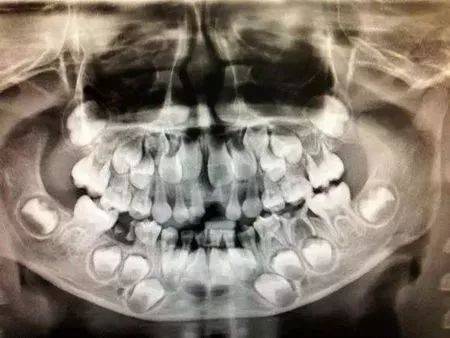

星期一早上,我坐在餐桌旁吃着香single的single头。单个bun头更难。我咬了一下bun头,用力拉了一下,然后把那块咬了进嘴里。那一刻,我感到牙齿疼痛,不知道为什么会疼,所以我继续咀嚼,但我并没有感到放松,也没有用舌头抵住它。原来,下排前牙的右牙松动。我继续吃东西,担心牙齿会很快脱落,我母亲说:“没关系,掉牙是每个孩子都要经历的事情,不要害怕!”我松了一口气,向妈妈点了点头。用右牙小心地咬bit头,以免碰到松动的前牙。

午餐时,我吃了第二碗米饭,最后一口,我咬了一块硬的东西,是吗?有未煮熟的东西吗?我从书包中取出纸,将其摊在桌上,然后将米吐出在桌上。我想看看那是什么。我撕掉边缘上的小纸片,轻轻地将米切成薄片,只看到中间有一颗洁白的牙齿。我碰到了丢失的牙齿的位置。它是空的。确实是我的前牙不见了。 ,我喝了一口水,感到血腥的味道。

我伸出牙齿,将它们放在桌子上。我把剩下的扔到垃圾桶,然后用干净的纸包住牙齿,然后将它们放在书包里。我心想:回家后,把它保存为纪念,长大后,看看小时候的牙齿是什么样子!